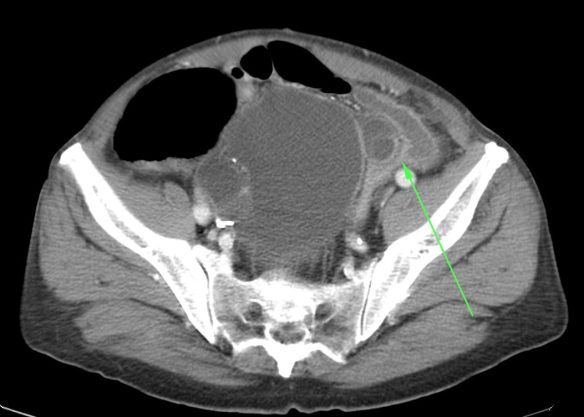

- El hallazgo patognomónico es el signo de la escarapela o diana identificable en la TC o ecografía.

- Podemos ver la imagen de «Intestino dentro de intestino” gracias a las reconstrucciones multiplanares.

Aunque el diagnóstico es sencillo, la TC es insuficiente para determinar la causa subyacente. Existen una serie de hallazgos que nos permiten caracterizar la invaginacion y valorar la gravedad, lo cual determina el tratamiento a seguir.

- Punto guía reconocible